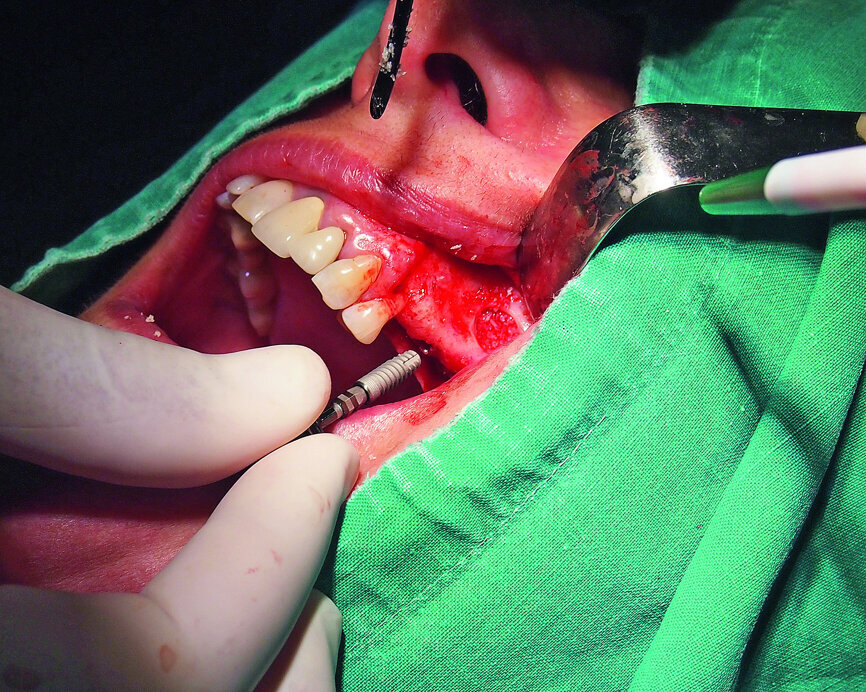

Fig. 7: Placement of a GC Aadva Standard 3.3 x 12.0 mm implant in the premolar region after the sinus graft.

Fig. 8: Placement of a GC Aadva Standard 4.0 x 10.0 mm implant in the molar region.

Therefore, we decided to perform a sinus lift by a lateral-wall approach. The Schneiderian membrane was elevated and protected with a collagenous high-density fleece (PARASORB Fleece Genta HD, RESORBA) to allow the placement of a xenogeneic bone graft in the subantral area (Figs. 3–6). Two GC Aadva Standard implants, one of 3.3 mm in diameter and 12.0 mm in length and the other of 4.0 mm in diameter and 10.0 mm in length, were respectively placed in the premolar and molar regions (Figs. 7 & 8). The access window was covered with an absorbable collagenous membrane (PARASORB RESODONT Forte, RESORBA) and the flap was sutured with a polyvinylidene fluoride (PVDF) monofilament suture (RESOPREN 6/0, RESORBA; Figs. 9 & 10).